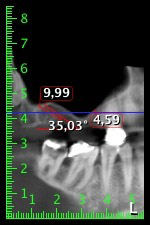

The 59-year-old patient presented with an advanced case of periodontitis, describing an unpleasant feeling and poor taste from the first quadrant in a distal direction. The clinical examination revealed generally enlarged periodontal pockets and very advanced bone atrophy in regions 16 and 14. The radiology confirmed the findings (Fig. 1). Teeth 16 and 14 could not be retained.

Image 1: Orthopantomogram with bone atrophy in region 16–14. *